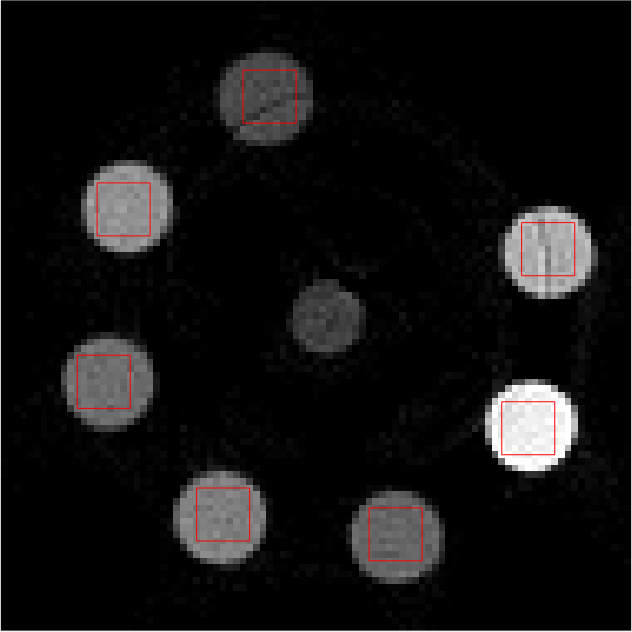

Individual reconstructions from every bin were first performed with scalar MBIR. This furnished 555 LAC images, each from a different energy bin. 101010 slices of each LAC image volume were used to compute \mathcal{M}. The mixing matrix was computed from ROIs shown in red in Fig 2. The following equation must be satisfied ideally

Refer to caption

(a)

(b)

(c)

(d)

(e)

Figure 2: Middle slice of LAC image reconstruction of each energy bin sinogram for mixing matrix estimation. Display window [0, 0.1]

LABEL:sub@fig:En1 Bin1:7.019.0keV7.019.0𝑘𝑒𝑉7.0-19.0\ keV, LABEL:sub@fig:En2 Bin2: 19.029.0keV19.029.0𝑘𝑒𝑉19.0-29.0\ keV, LABEL:sub@fig:En3 Bin3: 29.038.8keV29.038.8𝑘𝑒𝑉29.0-38.8\ keV, LABEL:sub@fig:En4 Bin4: 38.851.1keV38.851.1𝑘𝑒𝑉38.8-51.1\ keV, LABEL:sub@fig:En5 Bin5: 51.182.6keV51.182.6𝑘𝑒𝑉51.1-82.6\ keV